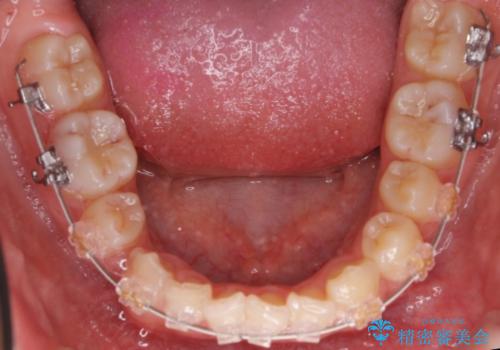

- 審美装置

その後、右下の小臼歯を1本抜歯し、ワイヤー矯正を行いました。

犬歯の代わりに小臼歯を配列し、最小限の抜歯の本数としました。

犬歯の両側の歯に関しては移動することにより歯槽骨が順調に回復し、上顎洞底の形態にかかわらず歯根のパラレリングを行うことができました。

犬歯の両側の歯に関しては移動することにより歯槽骨が順調に回復し、上顎洞底の形態にかかわらず歯根のパラレリングを行うことができた理由としては、年齢が10代前半と若かったからだと思います。

左上4−7については、近心傾斜をしていたため、右上3を抜かずに遠心に移動して非抜歯で治療を行う案も提案しましたが、抜歯を選択されました。結果的に深く埋まっていた右上犬歯を牽引せずにすみ、さらに歯根の向きも整えることができてよかったです。治療も比較的短期間で済みました。